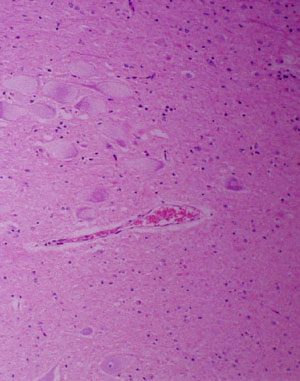

What is wrong with the appearance of these neurons?